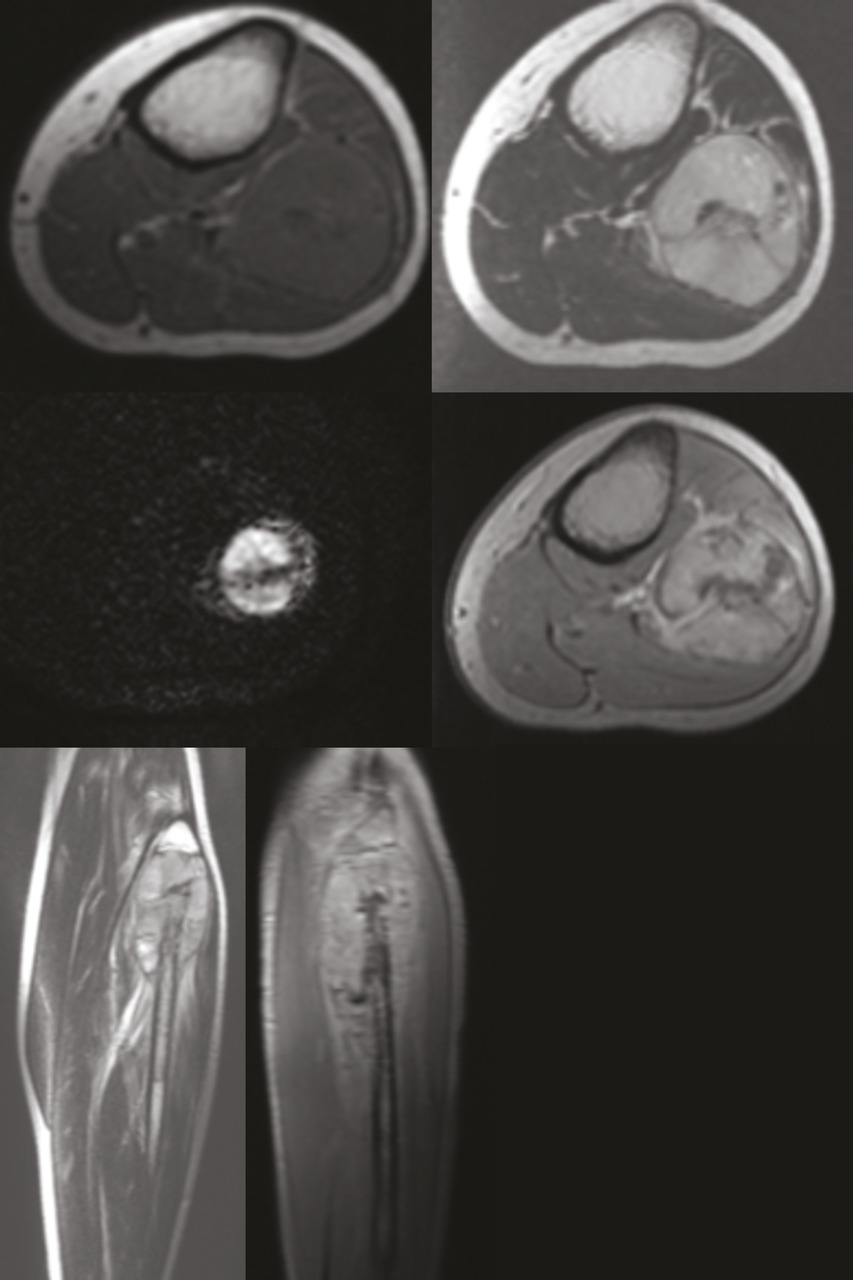

Un enfant de 14 ans, sans antécédents pathologiques particuliers, se plaint depuis un mois d’une douleur de la jambe gauche avec tuméfaction d’apparition progressive en externe. L’examen clinique trouve une masse fixe, de consistance dure et expansive dans la zone affectée sans autres signes pathologiques. Une radiographie montre un processus osseux centromédullaire expansif du tiers supérieur du péroné gauche avec une ostéolyse mitée et une réaction périostée en éperon de Codman (fig. 1 ). Une imagerie par résonance magnétique (IRM) décèle un processus tumoral osseux du tiers supérieur de la fibula centromédullaire métaphyso-diaphysaire se rehaussant de façon hétérogène après injection de produit de contraste ; ce processus envahit les parties molles adjacentes et respecte l’articulation tibio-fibulaire supérieure (fig. 2 ). Le diagnostic d’ostéosarcome est évoqué. Une biopsie est réalisée et l’étude anatomopathologique est en faveur d’un sarcome d’Ewing. Le scanner thoraco-abdomino-pelvien pratiqué ensuite pour rechercher d’éventuelles lésions métastatiques est normal. L’enfant a bénéficié d’une chimiothérapie néoadjuvante.